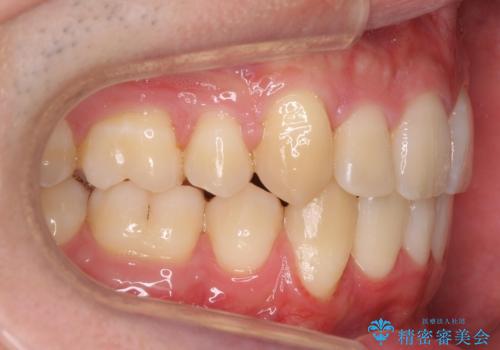

前歯のがたつき 下の八重歯

- 前歯のがたつきを主訴に来院。

上下左右の小臼歯を抜歯しています。

下のがたつきが大きいため、抜いたスペースをしっかり利用して並べるため矯正用インプラントを使用しています。

上下の前歯の重なりが大きく(過蓋咬合)時間がかかりましたが、しっかり浅く仕上げることができました。

矯正をしてよかったと大変喜んでおられました。